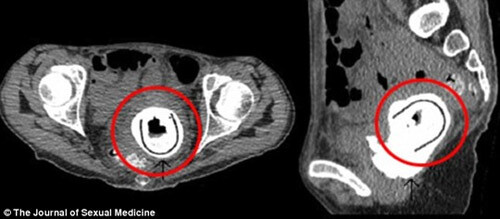

Theo bác sĩ Nguyễn Anh Tuấn, bác sĩ Nam Khoa BV Đa Khoa Hồng Ngọc: “Việc sử dụng đồ chơi tình dục giúp giải toả nhu cầu, tăng khoái cảm tức thời. Nhưng về lâu dài sẽ đem đến nhiều tác hại, nó sẽ tạo thành tiền lệ xấu, thói quen nguy hiểm. Đối với người độc thân, thường xuyên sử dụng đồ chơi tình dục khi lập gia đình, quan hệ tình dục sẽ mất cảm giác thật. Mặt khác, hầu hết đồ chơi tình dục bán ở Việt Nam đều không chứng minh đầy đủ nguồn gốc xuất xứ, chưa được kiểm chứng an toàn. Người sử dụng có thể bị đau rát, sưng tấy, dị ứng… thậm chí còn có thể bị viêm âm đạo, ung thư tinh hoàn vì các sản phẩm kém chất lượng”. Bác sĩ Tuấn cũng cho biết, anh đã tiếp nhận một số trường hợp bị sưng tấy dương vật vì sử dụng đồ chơi tình dục. Do tâm lý e ngại của người bệnh, nhiều người bị khá lâu mới đến khám bác sĩ dẫn đến hậu quả bị nhiễm trùng, liệt dương. |